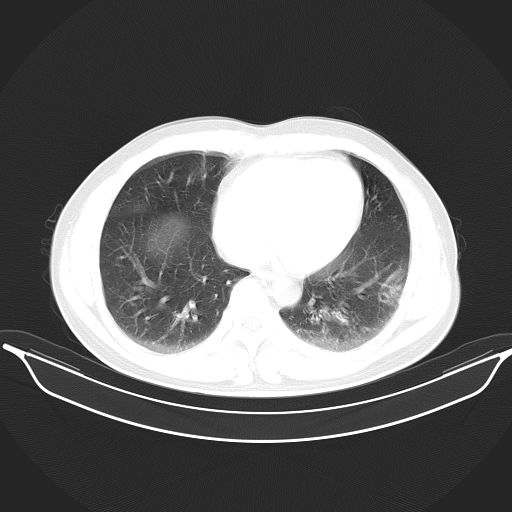

标题: CT25490:男,40岁,体检发现;无其它不适。 [打印本页]

标题: CT25490:男,40岁,体检发现;无其它不适。

倾向于结核

多考虑结核。

考虑结核

考虑肺霉菌病。

考虑右下肺周围性肺癌并肺内多发转移,纵隔淋巴结转移!

考虑过敏性肺炎,建议抗炎后复查,转移瘤及tb待排

支持 !考虑右下肺周围性肺癌并肺内多发转移,纵隔淋巴结转移,(气管前腔静脉后,隆突下,主动脉弓下都有了)